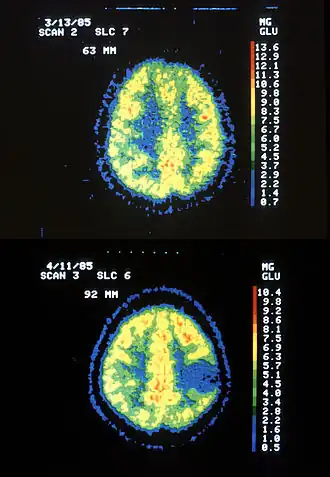

![]() Два ОФЭКТ изображения: верхнее показывает нормальный мозг, а нижнее — с астроцитомой. | |